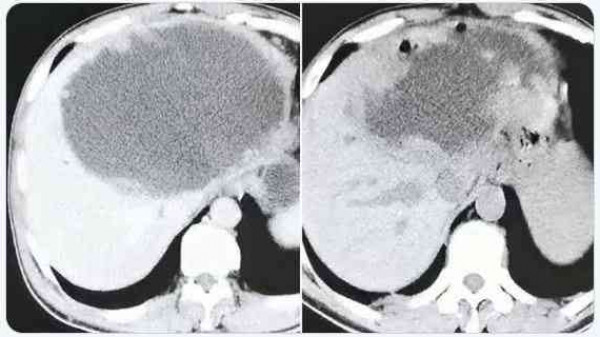

وذهب "شاي" إلى المستشفى بعد أربعة أشهر، عقب معاناته من قشعريرة وحمى شديدة لمدة ثلاثة أيام. وذهل الأطباء عندما اكتشفوا أن كبد المريض يحتوي على كتلة ضخمة مليئة بالصديد يبلغ طولها 19 سم وعرضها 18 سم، وفقا للتقرير.

وحاول الجراحون في البداية تقليل النتوء الاجتياحي مثل الكيس، عن طريق تجفيف الكتلة من السوائل، ولكنهم أدركوا بسرعة أن العدوى شديدة جدا، وقرروا قطع نصف الكبد.